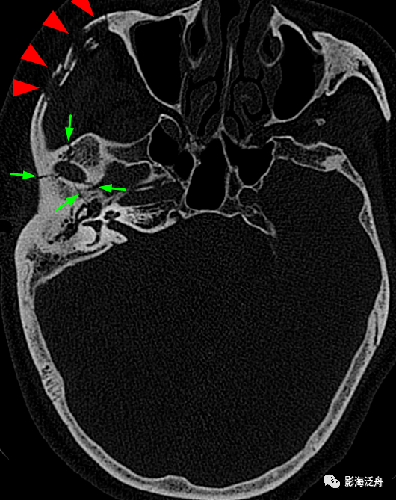

颅骨骨折是头部骨骼出现的一种骨折症状,主要是指头部骨骼的一块或者多块出现的断裂,可以分为很多种,比如为线形骨折、凹陷骨折、粉碎骨折等等,一般主要是由于钝性冲击造成的,一般来说对于患者的危害很大,主要是指颅骨骨折的并发症是致命的。

颅骨骨折的症状表现是有很多的,根据患者的不同具体骨折类型,会有不同的症状表现。比如线性骨折,容易引起脑损伤以及颅内出血,一般多见于儿童之间,对于患者生命危害很大的。

颅骨骨折中还有一种闭合性凹陷骨折,一般是多见于头顶部位以及额头部位的,多数是闭合性的损伤,患者的头皮是完整的,如果是粉碎性的凹陷骨折,则会伴随着脑组织损伤等症状。

开放性凹陷骨折也是很常见的,一般是由于外部的强大打击造成的,受累部分很多,比如头皮、颅骨、硬脑膜等等。